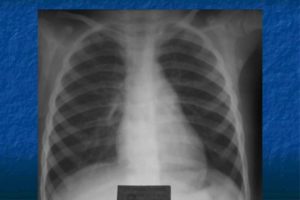

Легкие: в медиальной части снимка (возле позвоночника) видны корни легкого – сосудисто-бронхиальная структура средней плотности и разнородной структуры. Легочные поля, представляющие собой проекцию легких на плоскость, в норме обладают хорошей прозрачностью и не содержат посторонних теней. Правое легкое немного короче и шире, в то время как левое – уже и длиннее.

Как выглядят здоровые легкие на снимке?

Здоровые легкие на изображениях, полученных при компьютерной томографии, выглядят как однородные структуры без каких-либо признаков диффузных или очаговых изменений. Плевральная полость должна не содержать лишней жидкости, быть без сращений и спаек.